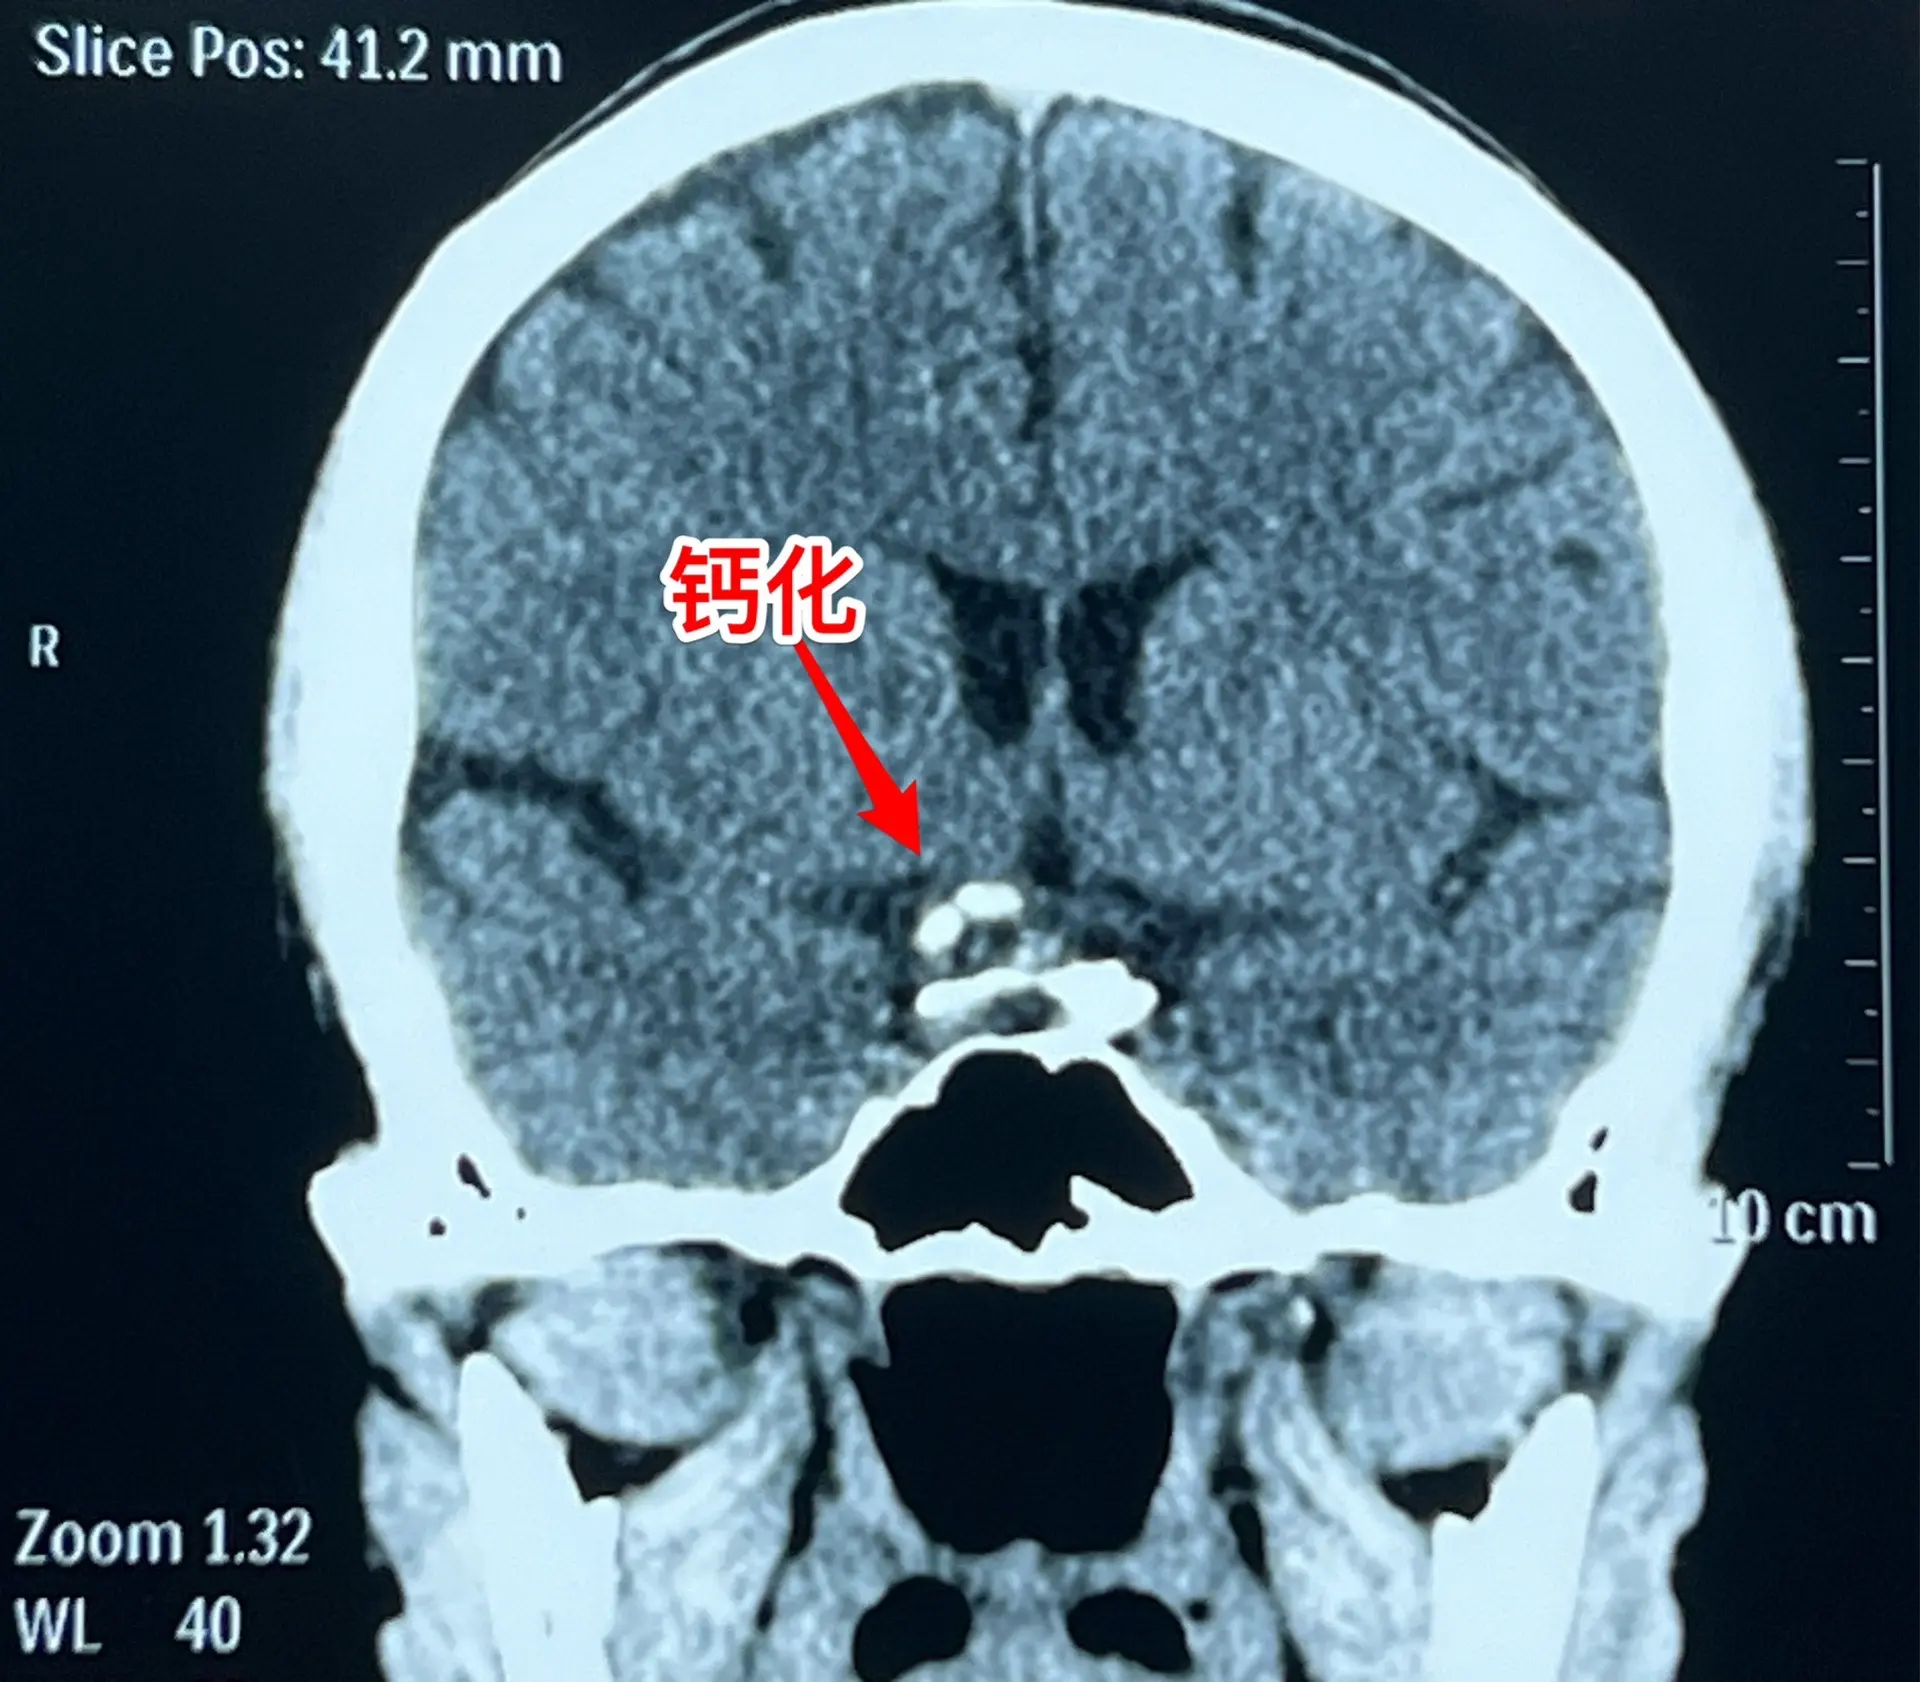

颅咽管瘤与拉克氏囊肿好鉴别吗?典型的造釉细胞型颅咽管瘤有钙化,与拉克氏...

2024-09-08 13:22